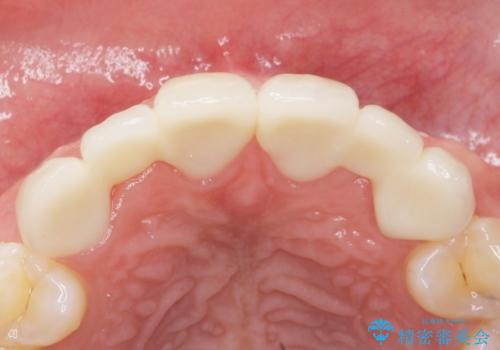

矯正以外の治療法で早く治したいとのご希望により、上顎両側犬歯を抜去しオールセラミックのブリッジによる補綴治療を行いました。

自然な仕上がりにご満足頂けました。

クラウンの種類:オールセラミッククラウン スタンダード